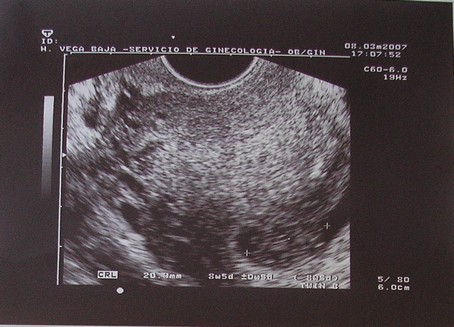

Ma voltam a másik dokinál...megnézte a bébit, és azt mondta minden ok, kora szerinti méretekkel rendelkezik.

Viszont nem kaptam képet,pedig kértem...azt mondta,az UH nem arra van hogy a kismama gyönyörködjön.

Meg sem mutatta a képernyőn sem a babát...még szerencse,hogy úgy felejtette a monitort én meg gyorsan megnéztem.

Édes nagyon a picike.